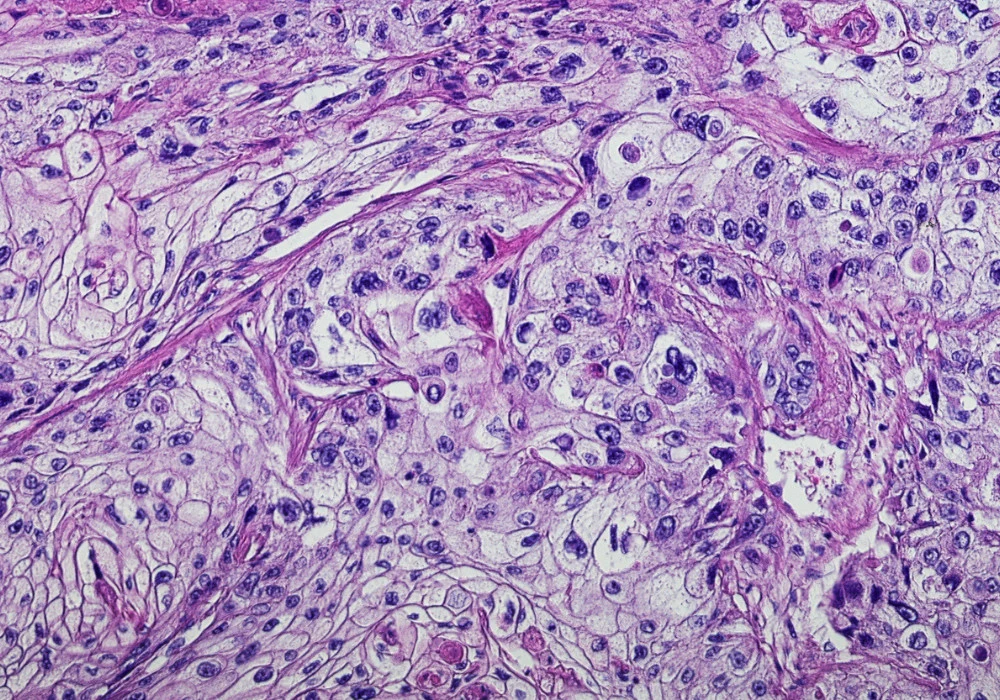

Whole slide images in digital pathology capture detailed tissue morphology but their gigapixel scale creates computational and annotation barriers for routine automation. A multimodal approach that combines these images with information contained in pathology reports promises gains in accuracy and consistency without exhaustive pixel-level labels. MPath-Net, an end-to-end framework that fuses image features from multiple-instance learning with text embeddings from transformer models, targets tumour subtype classification across kidney and lung cancers using publicly available data. Reported performance improvements over established unimodal and multimodal baselines underscore the value of integrating visual and textual signals for decision support in cancer diagnostics and workflow efficiency.

WSIs are preprocessed into tissue-containing patches and filtered to remove background using an edge-based criterion. Multiple-instance learning treats each slide as a bag of instances, enabling weak supervision when patch-level labels are unavailable. In this context, the slide label supervises learning while the model reasons over patch embeddings to infer slide-level subtype. This setting mirrors clinical practice where image patterns and narrative reports are considered together to delineate tumour characteristics and support subtype assignment.

Interpretability is addressed through attention heatmaps that highlight regions of interest at patch level on whole slides. Normalised attention scores mapped to colours help localise tumour-suggestive tissue, offering a visual explanation aligned with pathologist reviews. Illustrations compare attention patterns from baseline MIL models with the multimodal output, showing concentrated regions where tumour evidence is strongest. This transparency supports potential clinical utility by aligning model focus with tissue areas that drive classification decisions.